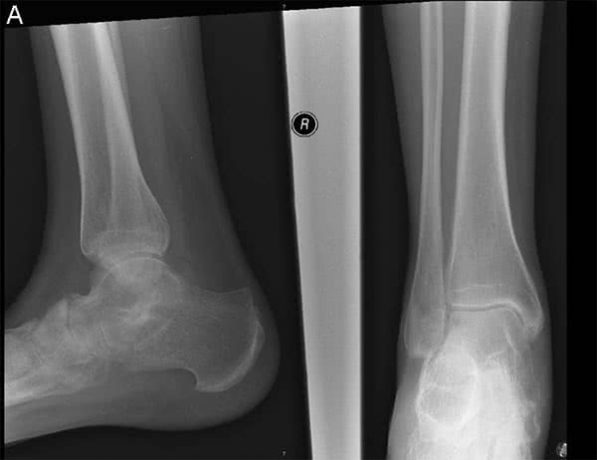

Анкилозом могут быть поражены такие мелкие и крупные суставы:

- Голеностопный.

Локтевой и плечевой суставы поражаются во время травмы, бедро — после перенесённого туберкулёза или длительного пребывания в неподвижном состоянии, голеностоп — в результате травмы или инфекции. Если повреждённый во время травмы сустав голеностопа неправильно (или недостаточно) лечили, то щиколотка перестаёт выполнять свои функции, и стопа перестаёт двигаться.

Основа распознавания анкилоза – визуализирующие методики, такие как рентгенография костей и суставов, компьютерная или магнитно-резонансная томография. С их помощью определяется сужение и прерывистость суставной щели или ее полное заращение.